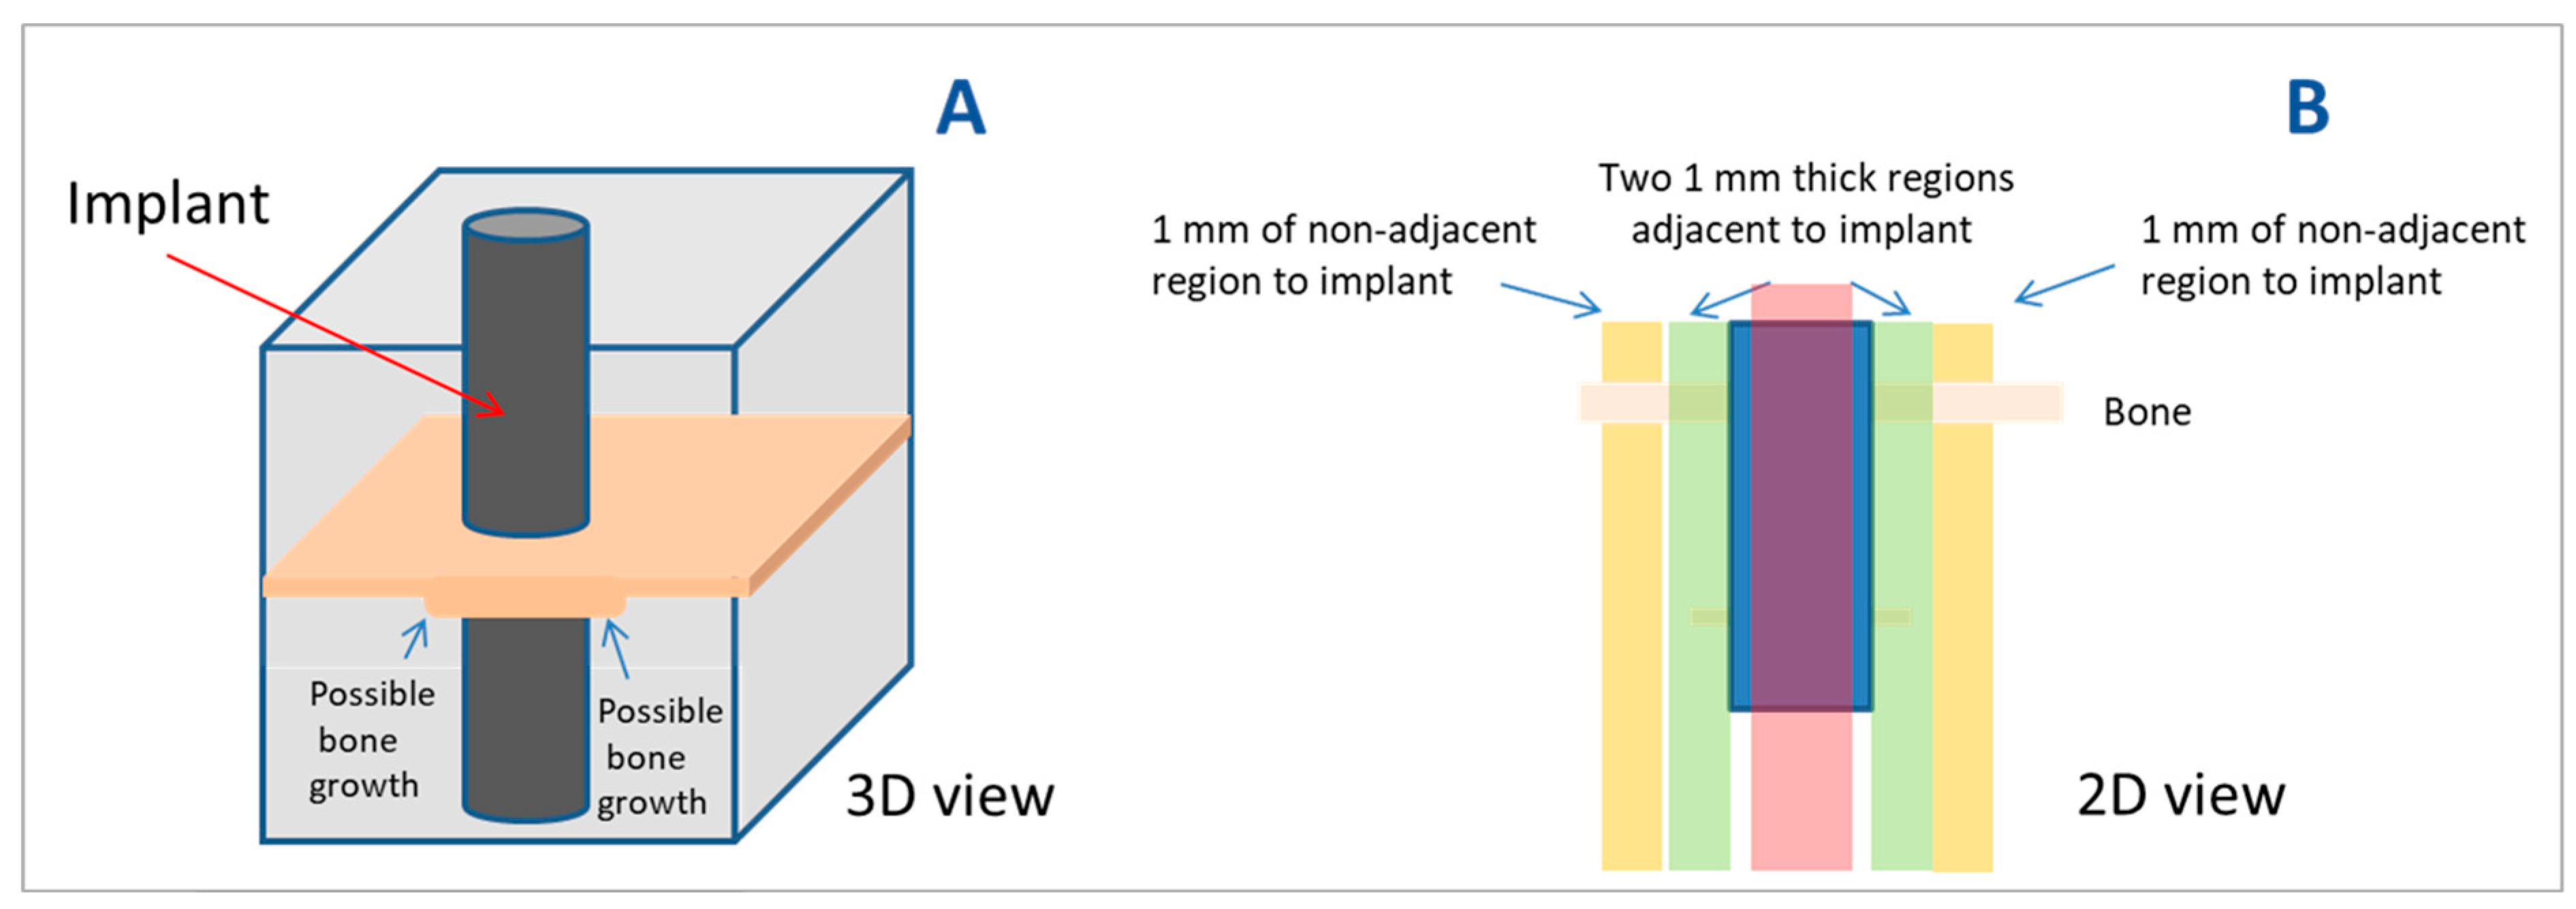

2.6. Histomorphometric Analysis

2.7. Statistical Analysis